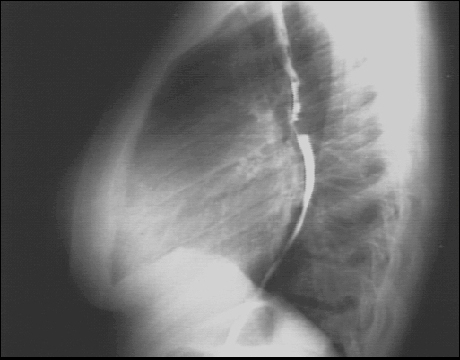

PA and Lateral

Click on the xrays to enlarge them.

Choose the best interpretation of the chest X rays:

Left atrial enlargement and right ventricular enlargement

Left ventricular enlargement and pulmonary congestion

Calcified mitral annulus

Left ventricular enlargement and dilated aorta

Left ventricular enlargement and left atrial enlargement